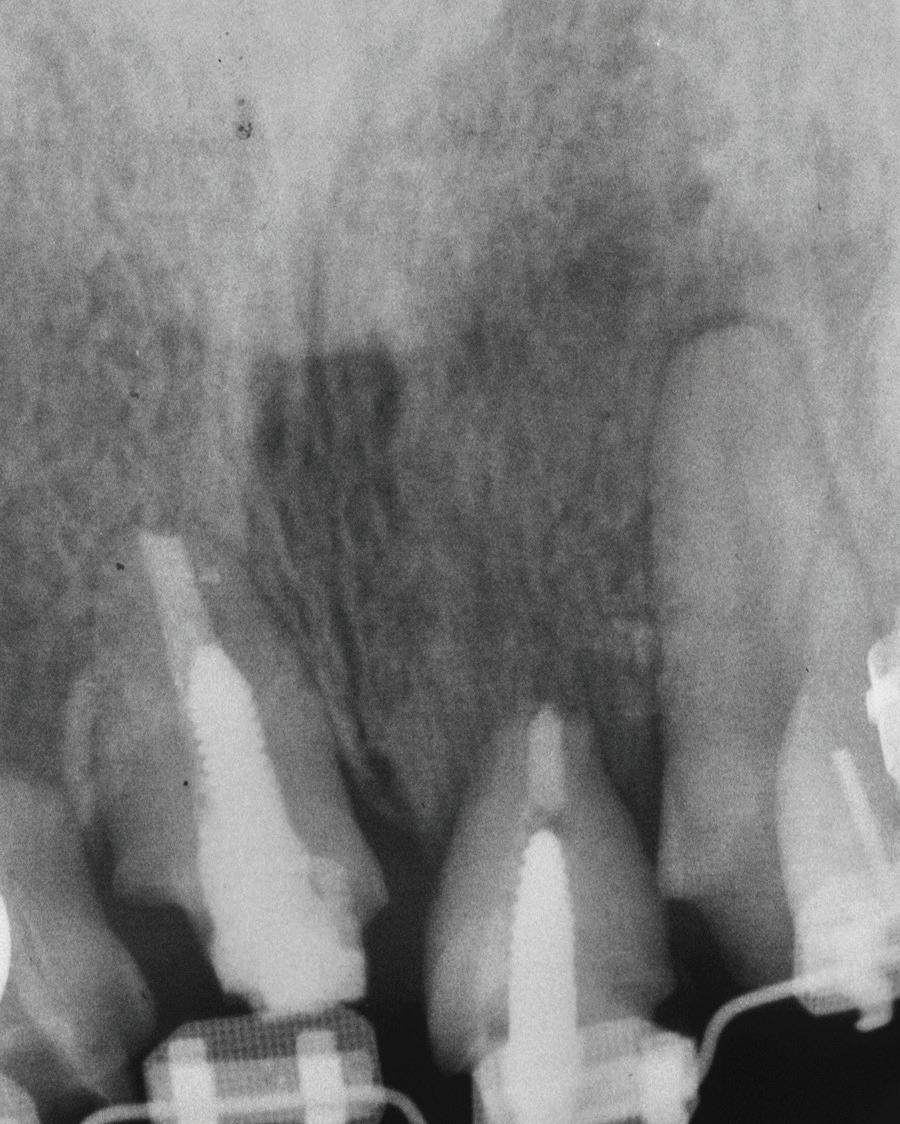

Un pacient caucazian în vârstă de 77 ani s-a prezentat la clinica autorului după cinci ani în care nu a fost la niciun control stomatologic. Examinarea clinică a arătat o pierdere semnificativă de os, parodontită cronică și multiple edentații care au destabilizat ocluzia. Pacientul a raportat sensibilitate la rece la nivelul primului molar drept inferior nr. 46, în special la ingerarea de lichide reci. Radiografia periapicală a confirmat constatările examenului clinic; în

plus, s-a detectat și prezența unei carii radiculare la nivelul rădăcinii distale a aceluiași molar, cu răspuns pozitiv la testul de sensibilitate (fig. 1-2).

Planul de tratament a început cu accent pe restabilirea sănătății parodontale. Într-o ședință ulterioară, odată cu îmbunătățirea stării parodonțiului, s-a efectuat restaurarea molarului nr. 46. Sub anestezie la Spina Spix pe partea dreaptă și

Figurile:

1. Situația clinică inițială.

2. Radiografia inițială.